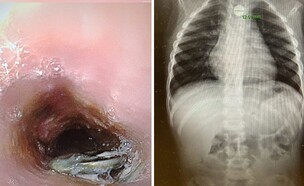

"יכולה להיות דלקת או כווייה כימית של הוושט"

ההורים דיווחו על תסמינים - והאבחנה שהגיעה

תופעת החורף המטרידה שפוגעת בילדים

צעירים מדברים על המחיר - רופאים מזהירים